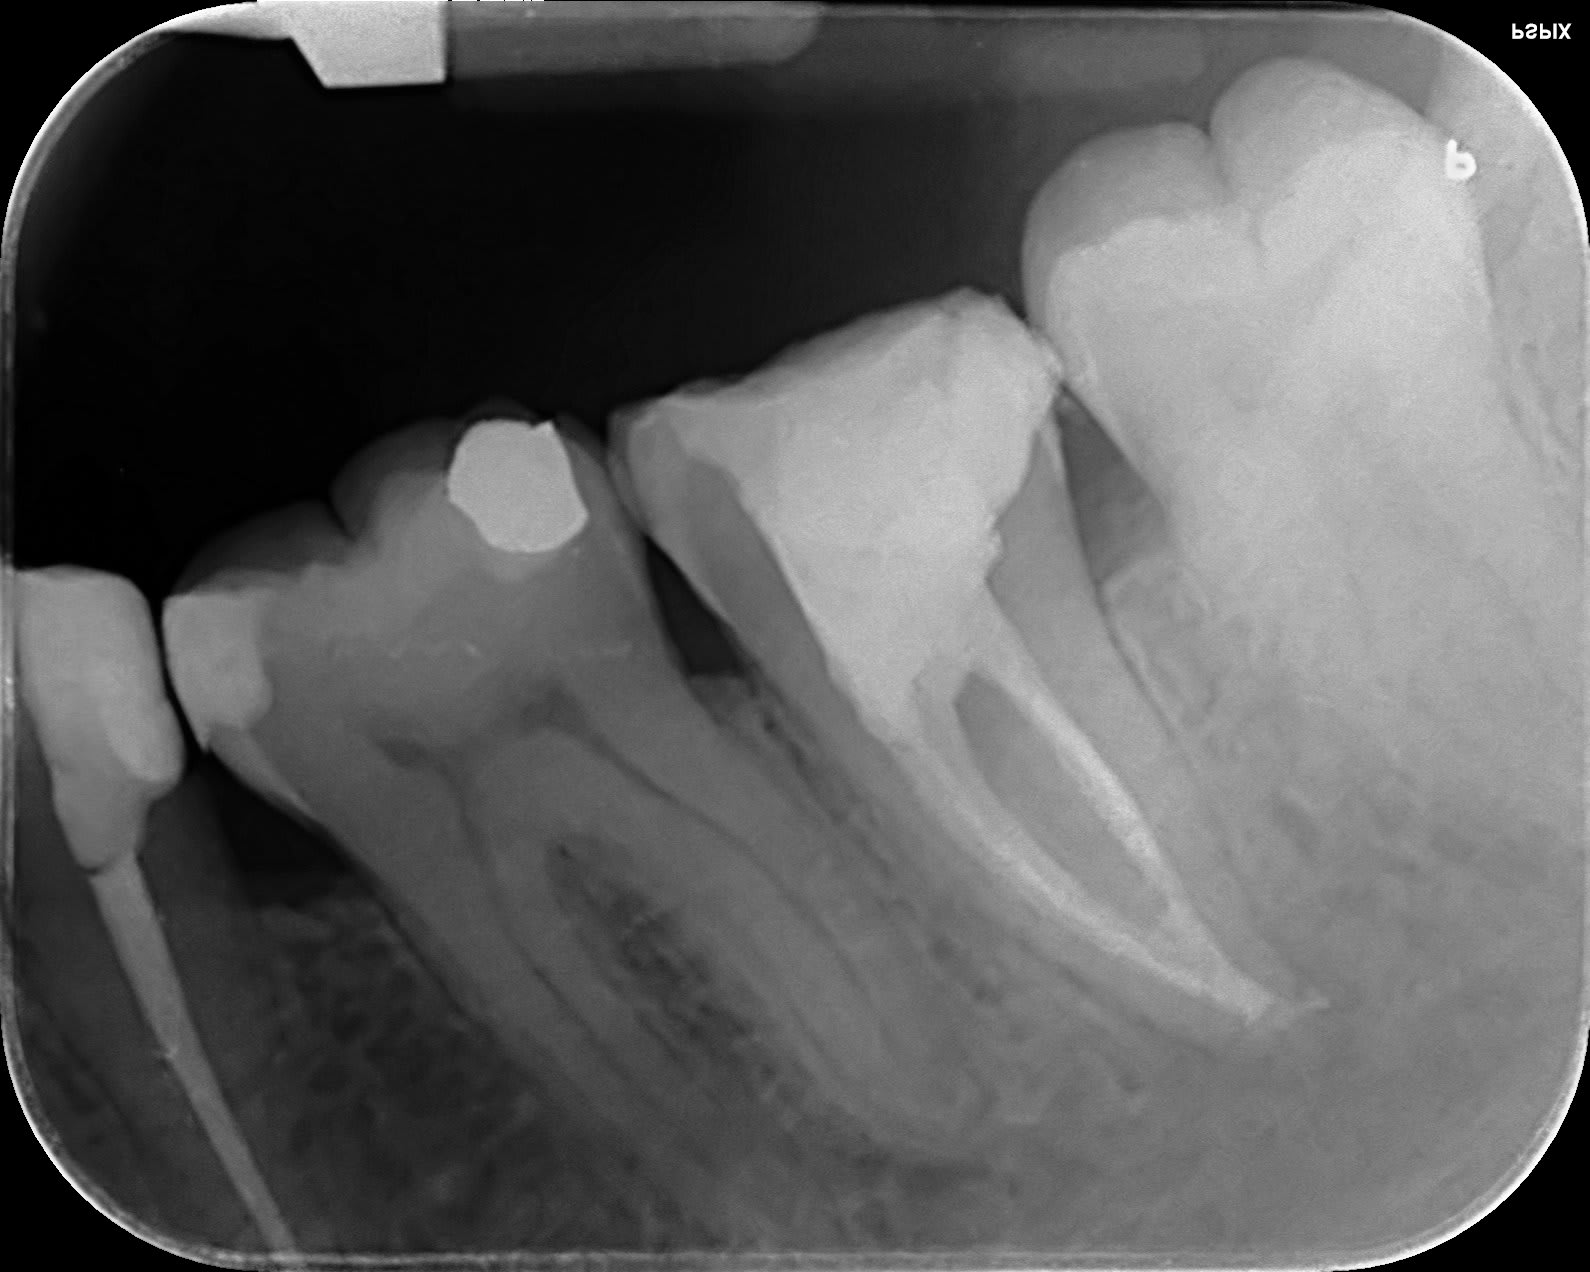

les Rx sont pas top, mais au final mon standard c'est ça.

J'ai repris la 5 ensuite.

Rob 1 ffmwtf - Eugenol

Rob 2 ou8kl6 - Eugenol

Rob 3 fgapwa - Eugenol